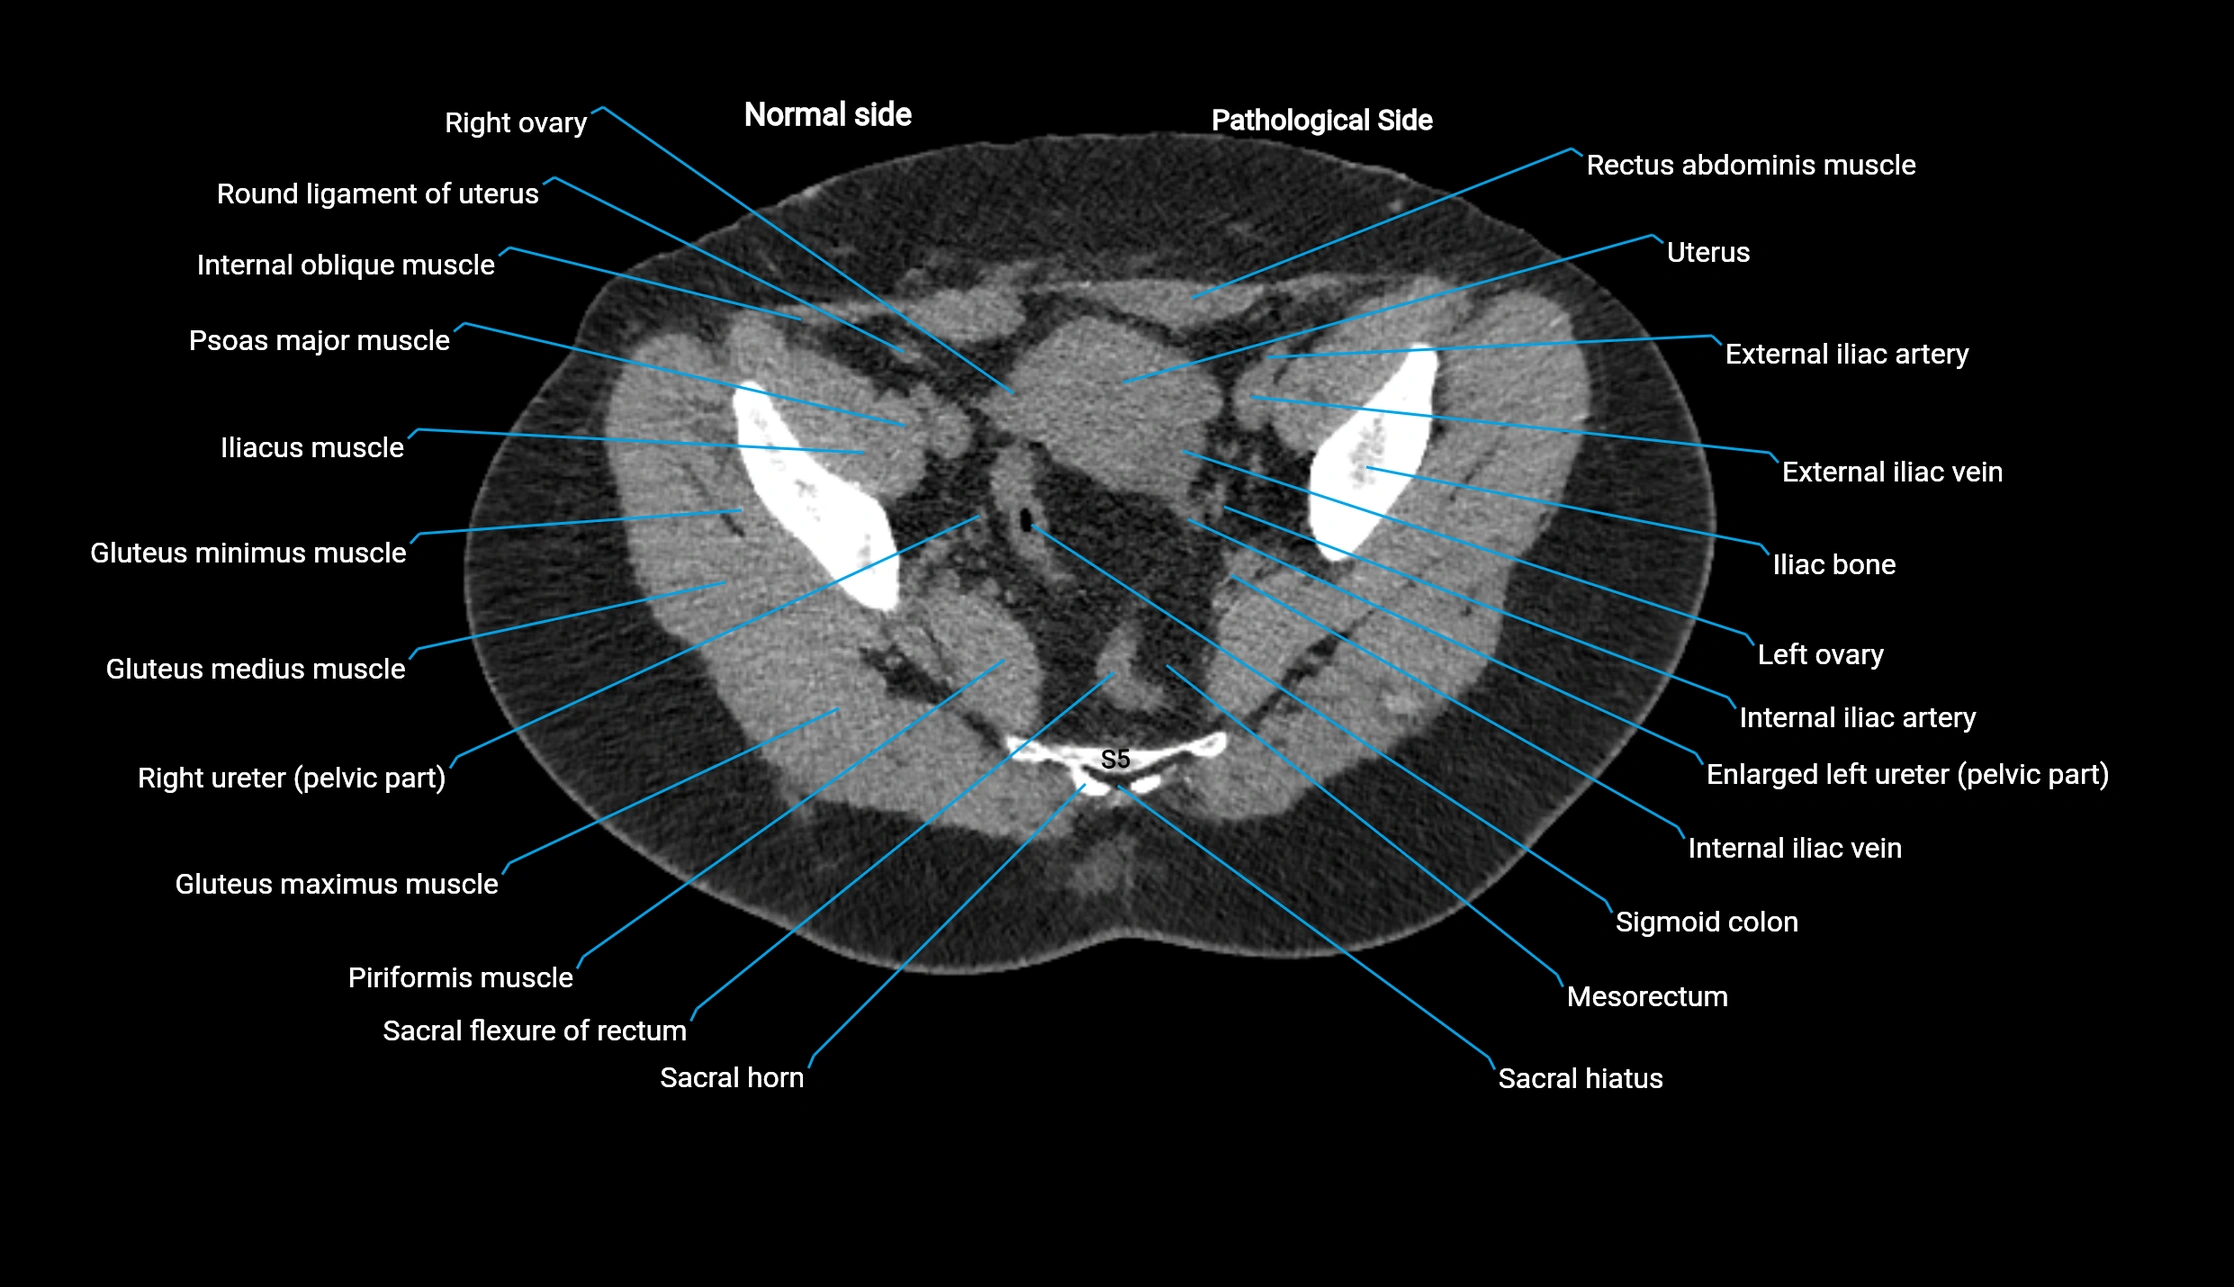

CT image

image